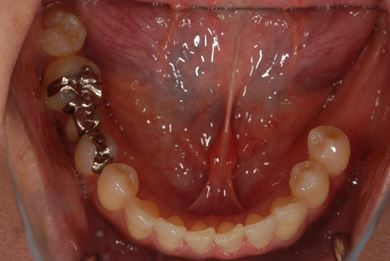

| 性別/年齢 | 女性 / 46歳 | ||||||||||||||||||||||||||||||||

| 主訴 | 左奥歯のインプラント治療を希望。 | ||||||||||||||||||||||||||||||||

| 治療方針 | 左下奥、欠損部分をインプラント治療にて、機能的・審美的回復を行う。 | ||||||||||||||||||||||||||||||||

| 治療内容 | インプラント2本、ハイブリッドセラミッククラウン2本 | ||||||||||||||||||||||||||||||||

| 総治療費 | 399,000円 | ||||||||||||||||||||||||||||||||

| 治療期間 | 5ヶ月 |